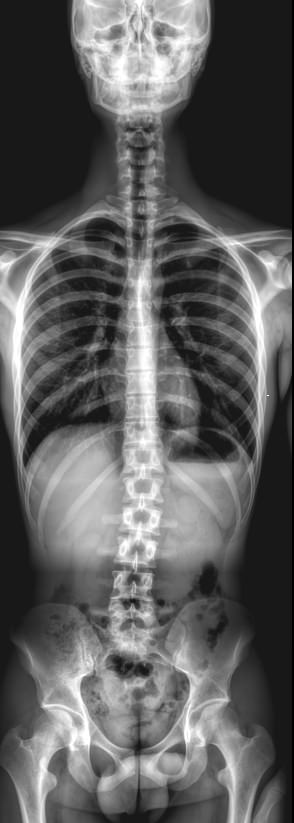

Потребность в рентгене всего позвоночника возникает при его патологическом искривлении ― сколиозе. Это стойкое отклонение позвоночного столба вбок, которое со временем приводит к серьезному искривлению всего скелета и нарушению работы внутренних органов. У взрослых такое заболевание может развиться в результате травм и болезней, но большинство случаев возникает в детском возрасте ― от 6 до 15 лет.

В развитии сколиоза различают 4 степени, которые отличаются величиной искривления, выраженной в градусах угла. Чтобы определить угол, врачу необходимо:

• Сделать рентгенограмму;

• Найти на ней 2 нейтральных, то есть не отклонившихся, позвонка, между которыми есть дуга искривления;

• Провести через них 2 горизонтальные линии перпендикулярно позвоночнику;

• Провести 2 вертикальные линии, перпендикулярные первым;

• Определить угол между второй парой прямых.

В прямом, то есть здоровом позвоночнике линии в парах будут параллельны друг другу, то есть угол составит 0о. При первой степени угол может доходить до 10о, при четвертой ― до 90о. Сколиоз первой степени почти всегда хорошо лечится.

Так как на один четкий снимок попадает не весь позвоночник, а только определенный сегмент, прибегают к стичингу ― склейке или сшивке нескольких снимков в один большой. Делается это виртуально, в цифровом поле, как и измерение углов, что гарантирует высокую точность и минимум погрешности. Переживать за высокий уровень полученной радиации не стоит: в современном оборудовании используется минимально возможное количество излучения. Даже при регулярном обследовании, которое рекомендовано при сколиозе раз в полгода, пациент не набирает допустимую ежегодную дозу.